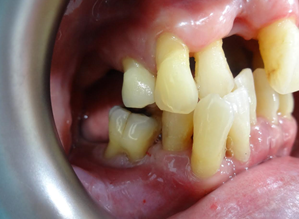

After the first therapy, there was total elimination of bad breathe and reduction in bleeding spot. Of course, I must complement his great effort in maintaining his oral hygiene. We repeated this procedure for another two times and review after 6 weeks, to allow gum healing. This is the result during review.

Gum appeared pinkish and healthy. No more gum bleeding, no more bad breathe, and teeth mobility was reduced. Clinical examination also showed great improvement. However, the lower front teeth are still loose, but no more bleeding.